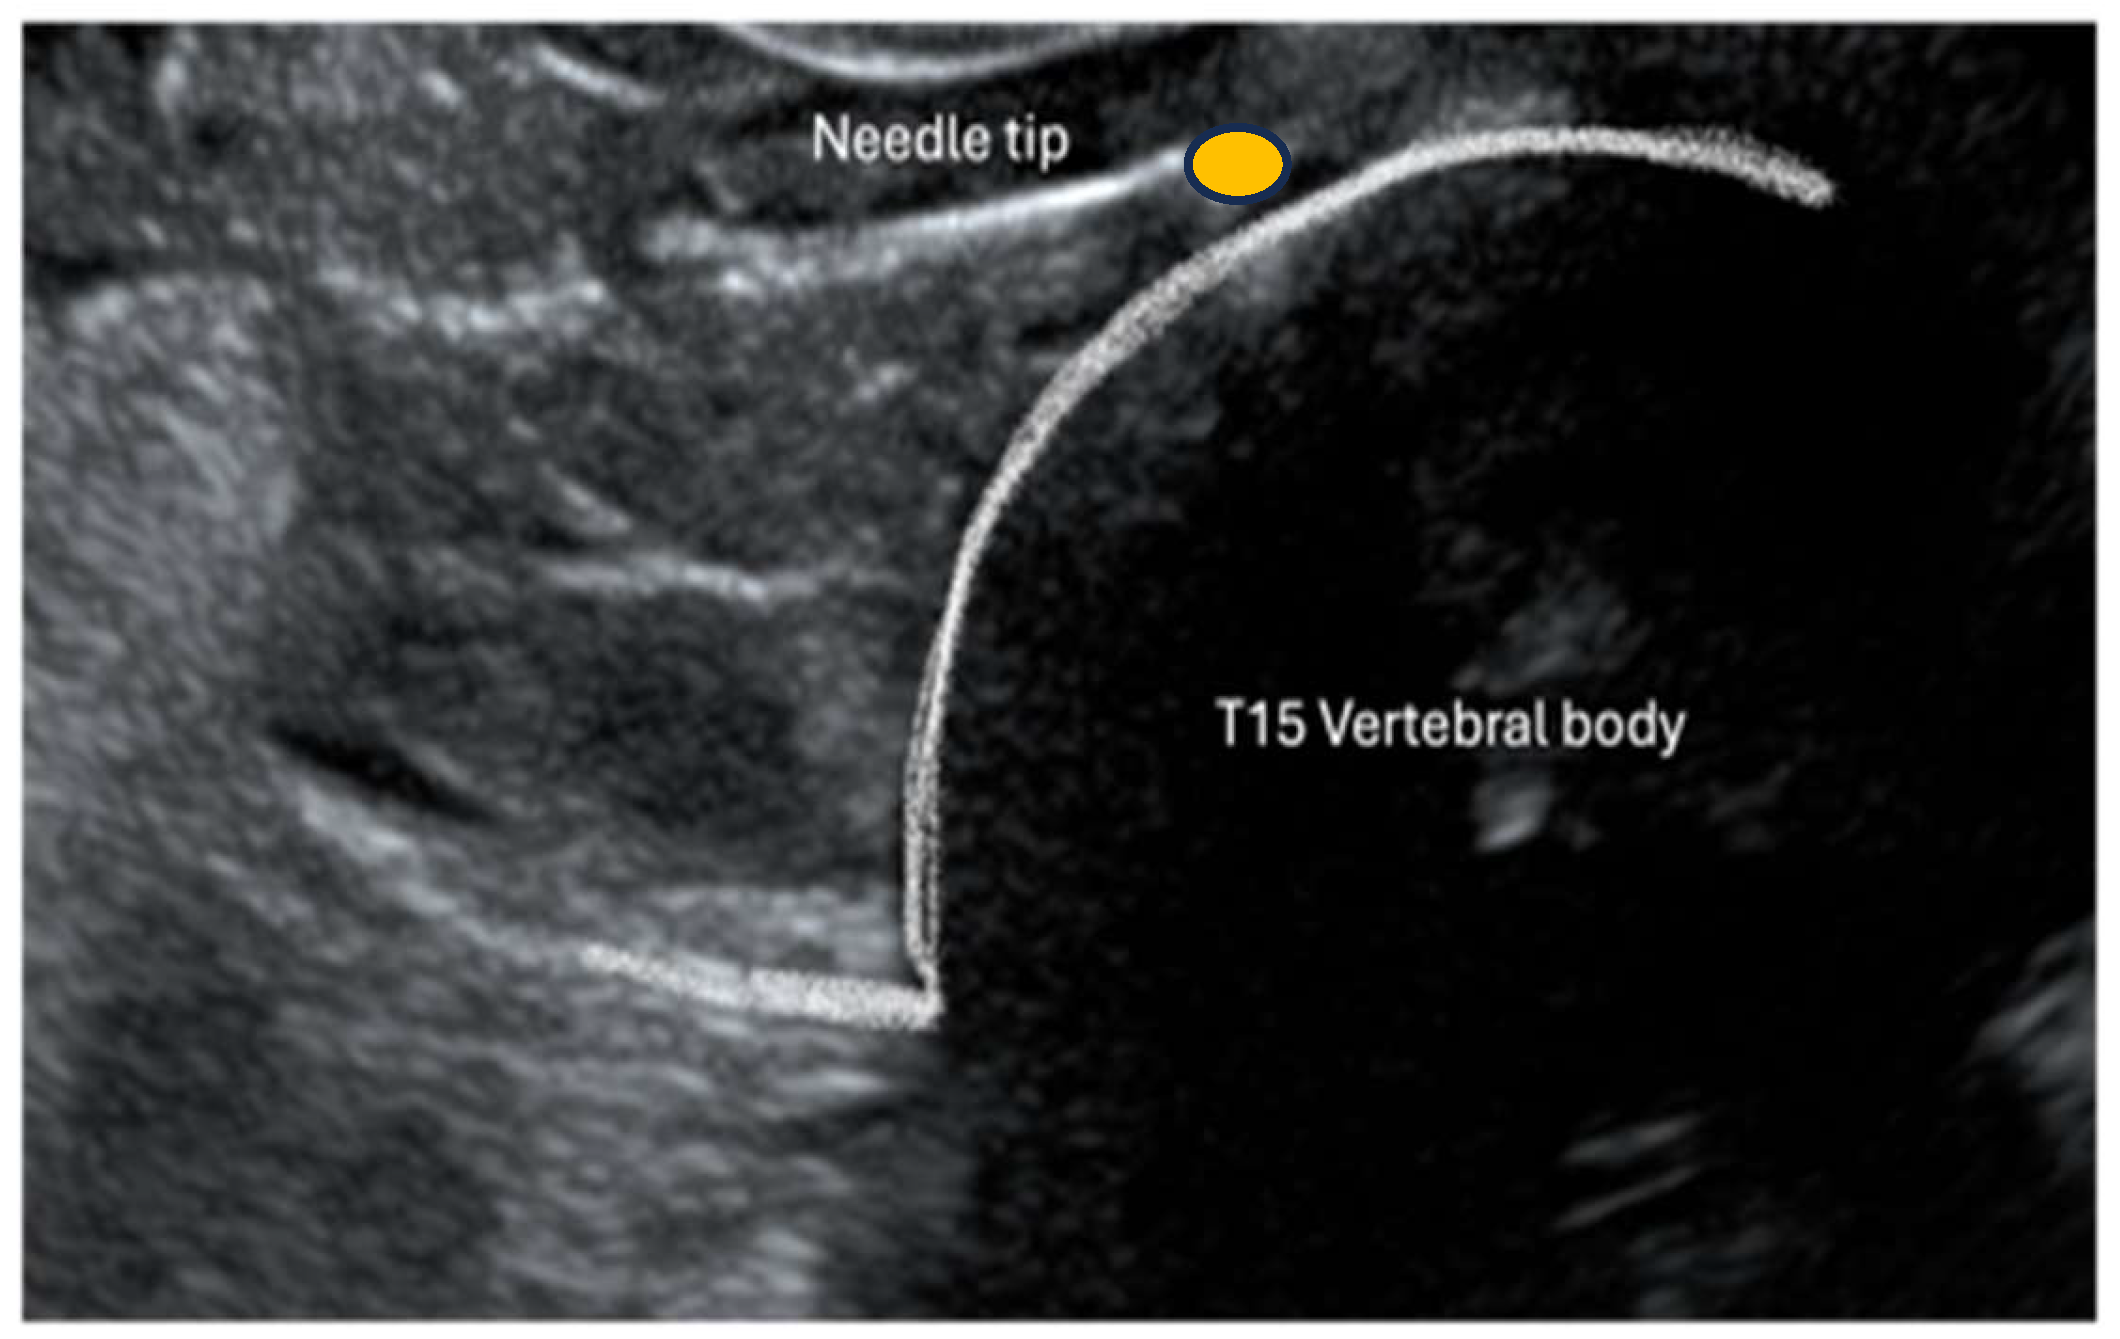

Cadavers were positioned in right lateral recumbency. A convex transducer (C11, 3s, Mindray M9 GI, Shenzhen, Guangdong, China) was placed on the craniodorsal aspect of the abdomen at the subcostal level just below the last rib (Figure 1). The transducer was gently slid and tilted to identify, in a transverse (short axis) view, the vertebral body of the last thoracic vertebra (T15). Under US guidance, an 18 G (120 mm) Tuohy needle was inserted percutaneously ventrally and parallel to the transverse process of T15 through the last intercostal space (Figure 1). The needle was advanced from dorsolateral to ventromedial through the epaxial muscle and approached the T15 vertebral body (Figure 2). Once the needle tip was in proximity to the lateral aspect of the T15 vertebral body, it was advanced towards the midline (Figure 3). Once the position of the needle was considered appropriate and no resistance to injection was felt, 2 mL of dye (China Ink, Pelikan Drawing Ink, Hanover, Germany) was applied.

Figure 2. Ultrasonographic image of the left cranial abdomen of the swine cadavers. The needle is inserted through the epaxial muscle, aiming at the vertebral body of the last thoracic vertebral (T15).